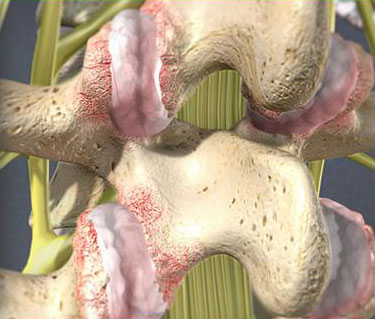

- Facet Joint Injections

Neck pain is a frequent issue for people affected by poor posture. It can also stem from overuse, wear and tear, injury, and many other potential factors. It can be challenging to recover from intense neck pain without the right professional help. We offer pain management and treatment options that can help to make life enjoyable and pain free once again.